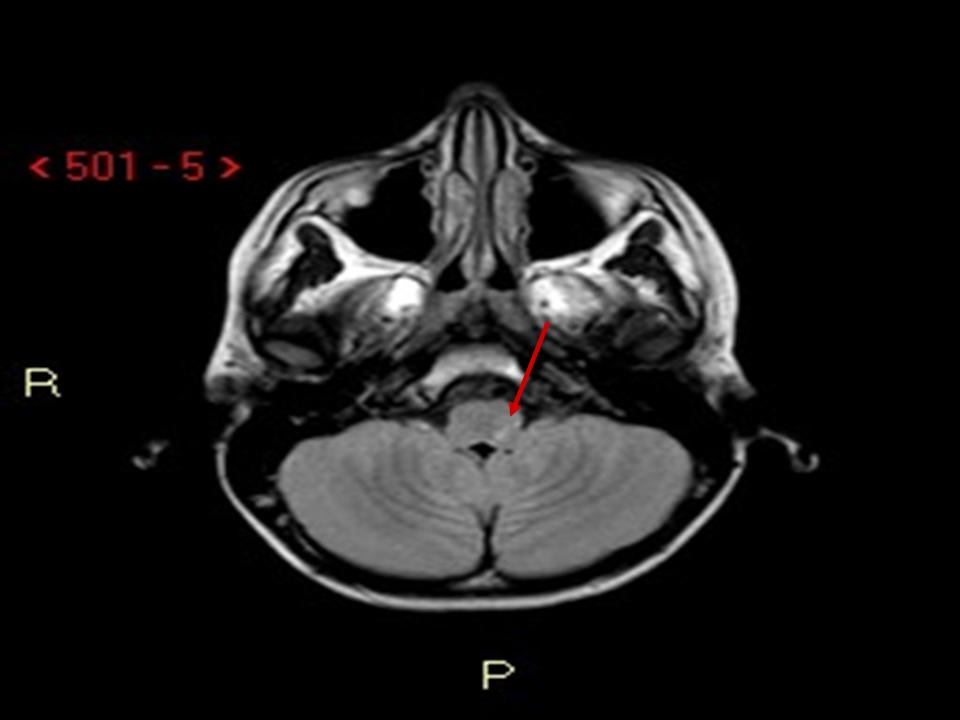

Figura

1. RMN. Assiale FLAIR (a sinistra): piccola lesione iperintensa a carico della porzione posteriore sinistra del bulbo compatibile con piccola lesione ischemica recente. DWI b1000 (a destra): piccola lesione a carico della porzione posteriore sinistra del bulbo con diffusione ristretta compatibile con piccola lesione ischemica recente.